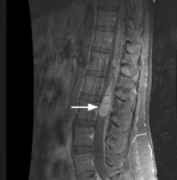

问: 什么是脊髓肿瘤 ?MRI核磁影像如何解读瘤种? 答:脊髓肿瘤是位于椎管(神经通道)中的神经和神经周组织肿瘤。根据肿瘤与脊髓和硬脑膜(包裹神经的膜)之间的位置关系...

Q:脊髓肿瘤是良性还是恶性? A:脊髓肿瘤指发生于脊髓本身、以及椎管内与脊髓邻近的肿瘤。 按肿瘤与脊髓关系,由内向外可以分为三类:脊髓髓内肿瘤,脊髓髓外硬脊膜下肿瘤,硬...